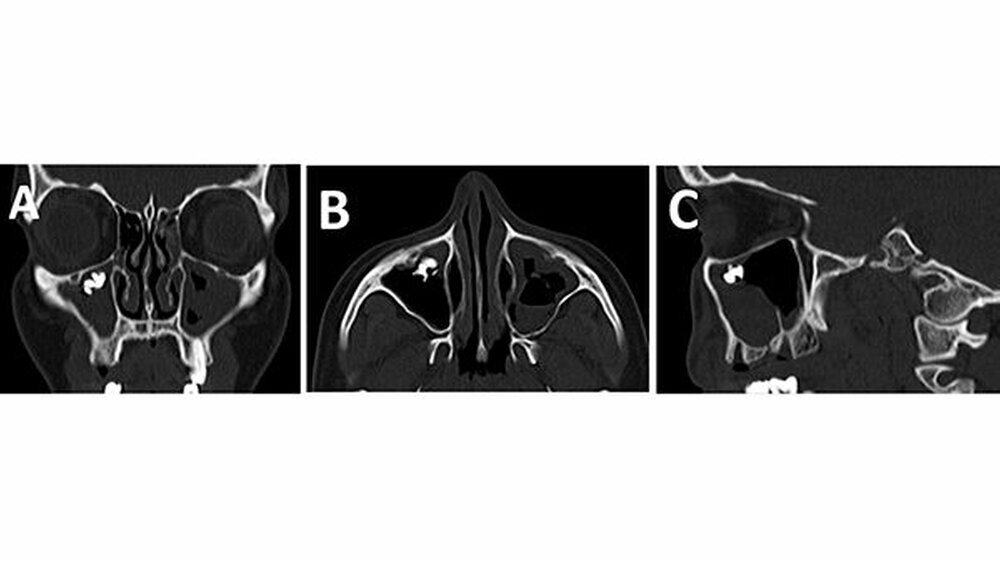

Das angefertigte Orthopantomogramm (OPT) stellte den aktuellen Zahnstatus mit dem Nebenbefund einer röntgendichten Verschattung im Sinne eines Fremdkörpers unterhalb des rechten Kieferhöhlendachs dar (Abbildung 1). Es folgte die Anfertigung eines NNH-CT zur genauen Lokalisierung des Fremdkörpers (Abbildung 2) für die anschließende OP-Planung.

In unserem Fall zeigte sich der röntgenopake Fremdkörper im OPT als Zufallsbefund. Zur genauen Lokalisation ist jedoch eine zwei- bis dreidimensionale radiologische Darstellung notwendig [Ferguson, 2014]. Bei der zweidimensionalen Darstellung bietet sich zum OPT ein Fernröntgenseitenbild und bei der dreidimensionalen ein DVT, NNH-CT sowie im Fall von nicht ferromagnetischen Fremdkörpern auch ein MRT an.